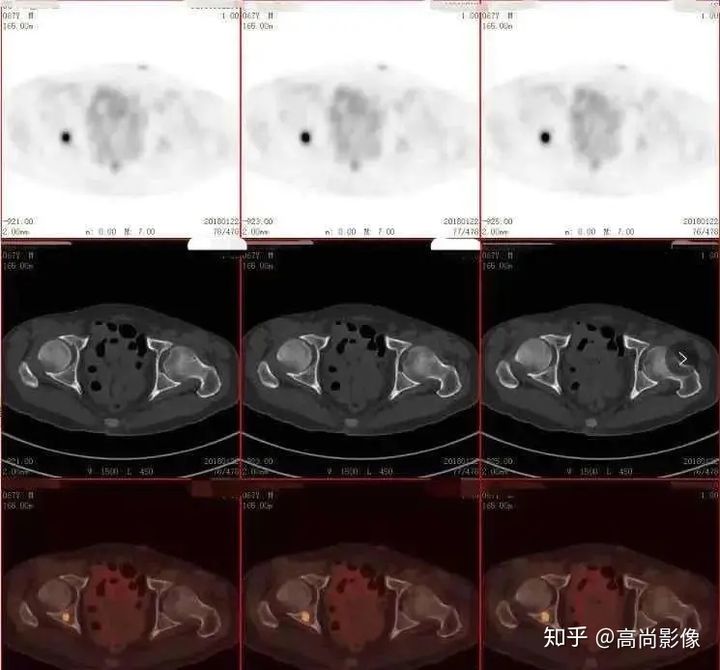

(右側(cè)髖臼骨轉(zhuǎn)移)

(右肺癌全身多發(fā)轉(zhuǎn)移)

(右肺上葉中央型肺癌)